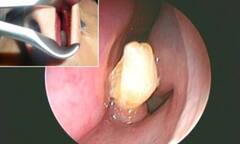

(ĐSPL) - Sau khi kiểm tra, các bác sĩ không khỏi kinh ngạc khi phát hiện có một chiếc răng dài khoảng 1cm mọc trong mũi nạn nhân.